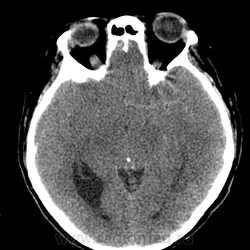

Больному около 55 лет, клинику дает не сколько само образование, а компрессия структур мозга, базально вообще беда (отчасти видно компреммию некоторых базальных цистерн мозга). Сразу скажу насчет эпидермоидной кисты - ДВИ не будет :)

Однозначно киста, значит, осталось выяснить какая, холестеатома или арахноидальная?

Эпидермоид может расти, при ТИА может быть случайной находкой. А тут ещё окклюзионная гидроцефалия.

Может, это две межполушарные арахноидальные кисты?